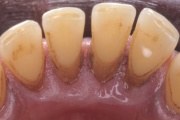

- igemed veritsevad (19)

- igemed punetavad (21)

- igemed on tursunud/vohavad (17)

- igemepiir on taandunud (3)

- puudulik suuhügieen (5)

- igemepealne hambakivi (5)

- igemealune hambakivi (4)